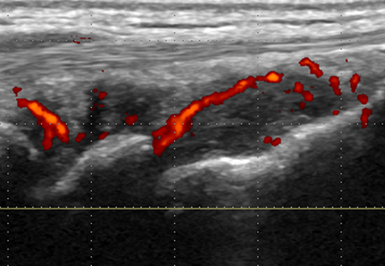

Der hochauflösende Ultraschall mit modernsten Geräten dient - ergänzend zur genauen Befragung (Anamnese) und der klinischen Untersuchung - zur Diagnose und gezielten ultraschallgesteuerten Punktion/Infiltration bei verschiedenen Erkrankungen des Bewegungsapparates.

Dabei lassen sich mittels Ultraschall strukturelle Schäden, akute Entzündungen oder sogar gestörte Bewegungsabläufe in der «dynamischen» Untersuchung darstellen. Aufgrund der ausgezeichneten Auflösung lassen sich mittlerweile auch kleinste Strukturen darstellen, punktieren und infiltrieren.